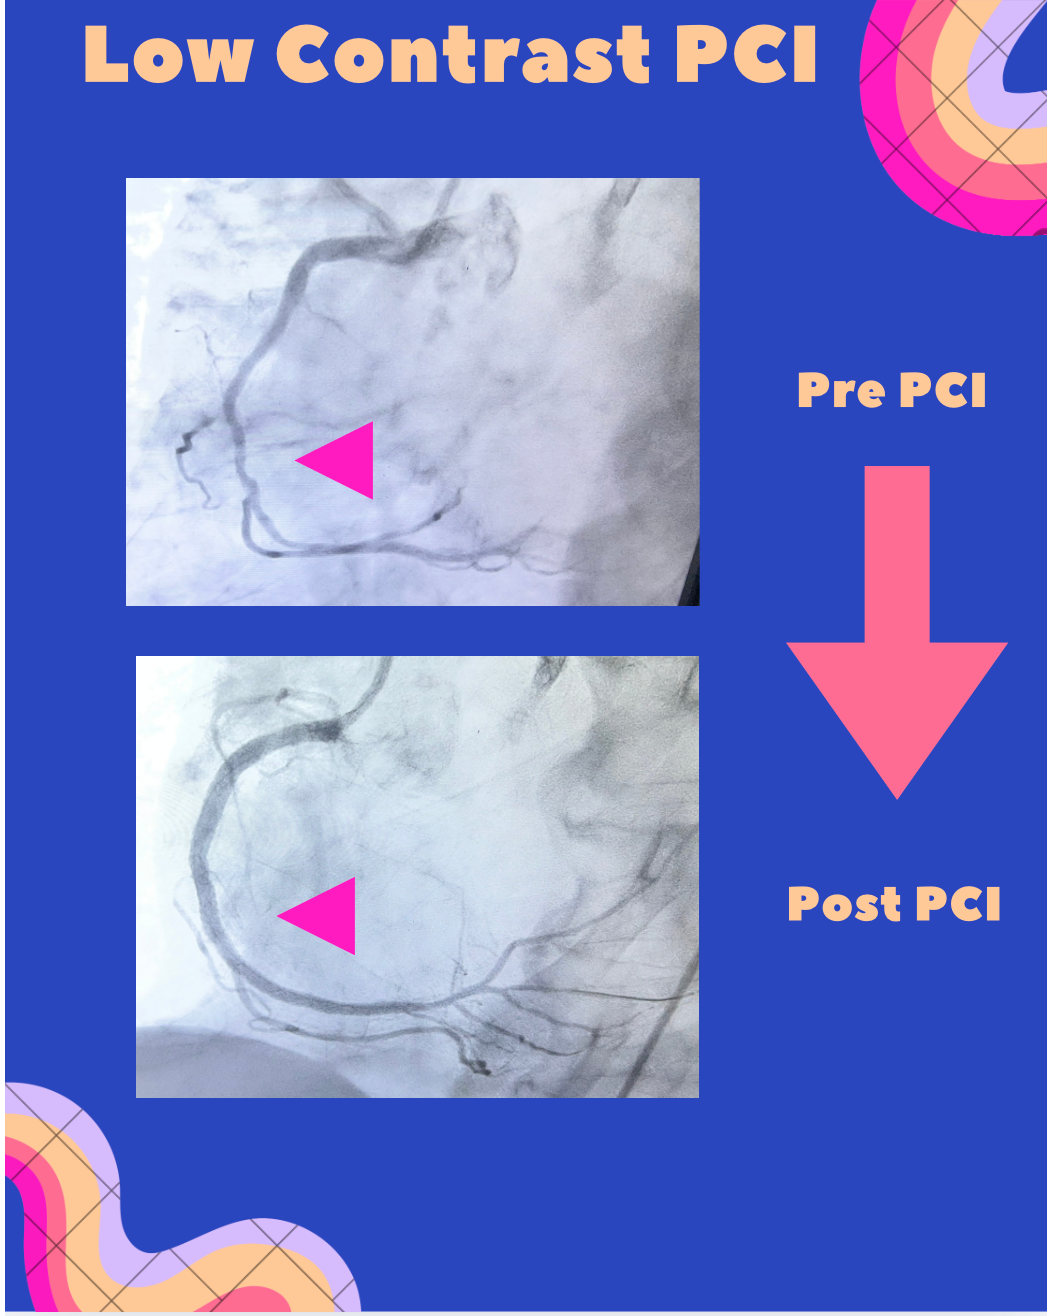

🫀 Heart Procedure with Minimal Dye: A Safer Approach for Kidney Patients in Navi Mumbai

Treating blocked heart arteries in patients with chronic kidney disease (CKD) can be challenging—because the contrast dye used during angioplasty can further harm the kidneys. 💡 Here’s where Low Contrast angioplasty makes a difference. Recently, in a patient with Kidney Disorder and a heavily calcified artery, a complex heart procedure was successfully performed using: ✔️ Minimal contrast dye to protect kidney function. ✔️ FFR (Fractional Flow Reserve) to accurately assess the severity of the blockage without excess dye ✔️ Guide extension catheter for better device delivery in a tough, calcified blockage This patient had Creatinine of 5.9 g/dl when this procedure was performed and wanted to avoid dialysis as much as possible. So this procedure was performed with accuracy, precision and Safety & patient was discharged on Day 3 following procedure. 🔍 Why this approach matters: • Reduces risk of contrast-induced kidney injury • Enables safe treatment of complex, calcified arteries • Uses physiology (FFR) to guide precise decision-making • Improves outcomes in high-risk patients ⚠️ Kidney patients undergoing angioplasty need special care and techniques like low contrast PCI are changing the game. 👉 A great example of how modern cardiology balances precision + safety, especially in vulnerable patients. 💬 If you or a loved one has kidney disease and heart blockage, ask your cardiologist about kidney-safe angioplasty techniques, or contact us at Anahatheartcenter.com, drrajeshmattacardio.com #CKD #HeartHealth #Angioplasty #LowContrastPCI #FFR #InterventionalCardiology #PatientSafety #CalcifiedLesions #MedicalInnovation